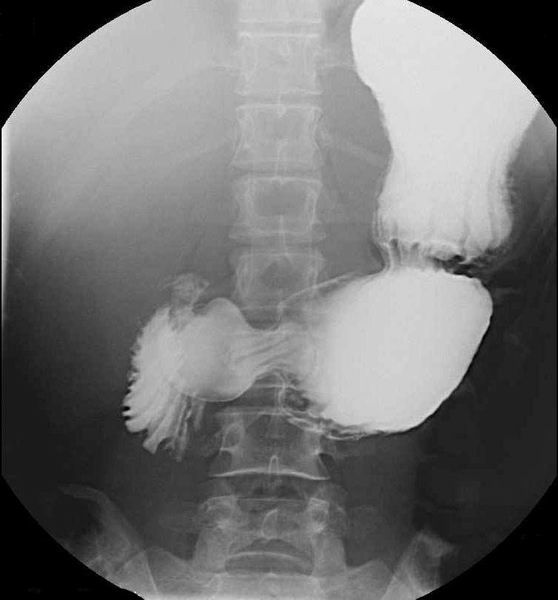

Colonografie